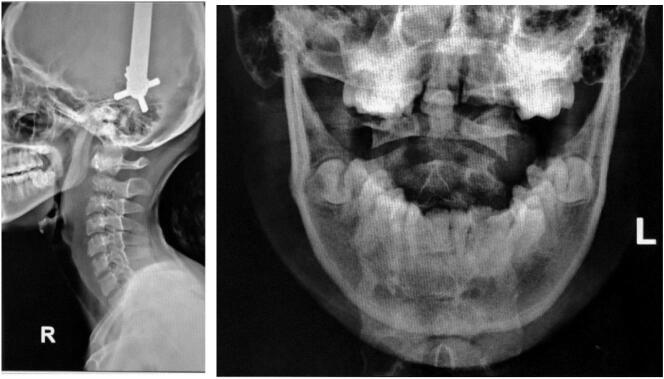

A 14-year-old girl came with sudden neck pain and difficulty moving her head that has worsened in the last 2 days. Previously, there was no history of cough, weight loss, fever over a long period, or suspicion of previous contact with TB. The patient felt a cracking sound on her neck before the sudden neck pain. There was no motoric weakness in her limbs. However, tingling in both hands and feet was felt. Previous neck pain was reported 3 months before the onset of acute pain. The local state of the neck showed deformity with a lump in the C2 region (Fig. 1, Fig. 2). The range of motion of the cervical spine was limited due to pain. The motor and sensory examination showed normal results despite urinary incontinence. Cervical X-ray examination in anteroposterior (AP) view, lateral, and open mouth, detailed with CT-scan, showed atlantoaxial dislocation with an odontoid fracture with atlantodental interval of 6.2 mm and space available for the cord (SAC) of 22.5 mm. Traction and immobilization using Garden-Well Tongs obtained the reduction of atlantoaxial dislocation (Fig. 3). Post-traction X-ray showed improvement in cervical spine alignment but no improvement in the ADI (Fig. 4). A computed tomography scan was then obtained, which confirmed type II odontoid fracture with the destruction of the C2 vertebral body and C6 vertebral body (Fig. 5). The patient was diagnosed with atlantoaxial dislocation with odontoid fracture type II due to suspected spondylitis tuberculosis infection.

X-ray examination of the cervical spine showed atlantoaxial dislocation with type II odontoid fracture.

Post-traction radiographic evaluation.